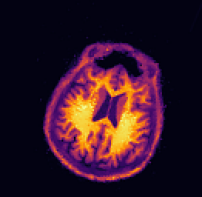

In our first experiment we perform multi-contrast MRI reconstruction from undersampled data. Since all contrasts are likely to share a structural information, less data is needed if the expected redundancy is exploited. Here we assume that a T2-weighted has been acquired using ”full data” and reconstructed without artefacts. We then use this image to reconstruct a T1-weighted image using only a fraction of the data. In this experiment we simulate the k-space data based on reconstructions of fully sampled clinical data.

The forward operator is a discrete Fourier transform defined on complex-valued images of size 256×256256256256\times 256, followed by a sampling operator corresponding to 15 equidistant spokes and a low-pass sampling of the 10×10101010\times 10 center of the k𝑘k-space. This yields a sampling of approximately 3%percent33\% of the k𝑘k-space. This sampling is easy to approximate on any clinical MRI scanner. The noise modelling here is Gaussian which is why we use the squared Euclidean norm (3) as data fidelity. The image domain is [1,1]2superscript112[-1,1]^{2} which corresponds to a pixel width of approximately 0.00780.00780.0078. The deformation field in this simulation is a rigid transform followed by zooming, given by

ϕzoom(x)=αRθx+bsubscriptitalic-ϕzoom𝑥𝛼subscript𝑅𝜃𝑥𝑏\displaystyle\phi_{\texttt{zoom}}(x)=\alpha R_{\theta}x+b

where Rθsubscript𝑅𝜃R_{\theta} is a rotation matrix (12) with angle θ=0.1𝜃0.1\theta=0.1, b=(0.02,0.08)T𝑏superscript0.020.08𝑇b=(-0.02,-0.08)^{T} is a translation vector, and α=0.85𝛼0.85\alpha=0.85 is a zoom factor. The latter means that the size of the side information image is only 85%percent8585\% of the size of the image which underlies the k𝑘k-space data. Since nonnegativity is not a meaningful assumption for complex-valued images, we drop this constraint in (10) for this test case. The resolutions and regularization parameters in Algorithm 2 were chosen as nk=(322,622,1282,2562)subscript𝑛𝑘superscript322superscript622superscript1282superscript2562n_{k}=(32^{2},62^{2},128^{2},256^{2}) and αk=5103(53,52,5,1)subscript𝛼𝑘5superscript103superscript53superscript5251\alpha_{k}=5\cdot 10^{-3}\cdot(5^{3},5^{2},5,1). For the TVTV\operatorname{TV} reconstruction we used αk=5104(53,52,5,1)subscript𝛼𝑘5superscript104superscript53superscript5251\alpha_{k}=5\cdot 10^{-4}\cdot(5^{3},5^{2},5,1). Here, and also for the following experiments, the resolutions were determined by successively dividing the resolution of the side information by a factor of two. The regularization parameters at the target resolution were chosen experimentally in order to maximize SSIM. Typically, the regularization parameter of TVTV\operatorname{TV} has to be chosen one or two orders of magnitude smaller than the one for dTVdTV\operatorname{dTV}.

The first row of Figure 3 shows the sampling pattern and the deformed image which was used to generate the data. Furthermore, it shows the side information and the ground truth image which we would like to reconstruct.

In the second row of Figure 3 we show the zero-filled reconstruction (pseudo-inverse), a standard TVTV\operatorname{TV} reconstruction, the result of the three-step method (22), and our proposed method. Obviously the pseudo-inverse and TVTV\operatorname{TV} method yield unsatisfactory results since the do not utilize the side information. Furthermore, they visualize the strong degree of ill-posedness of the problem where the sampled Fourier data alone cannot be used for a meaningful reconstruction. In contrast, both the three-step method (22) and our proposed method successfully correct the deformation between side information and data and yield good reconstructions despite the high degree of undersampling in the data. Notably, the proposed method yields better reconstructions of fine structures as can be seen in the zooms of Figure 3.

The previous observations are also supported by quantitative metrics. The SSIM values between the pseudo-inverse and TVTV\operatorname{TV} reconstruction and the deformed ground truth image which underlies the data are very low which is due to the strong undersampling. In contrast, the three-step method and the proposed method have high similarity values with the ground truth image, with slightly better numbers of the proposed method. Also the relative difference between the estimated affine deformation parameters and the ground truth parameters is lower for the proposed method than for the three-step method which underlines the superiority of our joint approach over the three-step method (22) in this application. We suspect that worse estimation of the deformation field of the three-step method is due to the fact that it must utilize the blurry and blocky TVTV\operatorname{TV} reconstruction for registration whereas the proposed method iteratively improves registration and reconstruction.